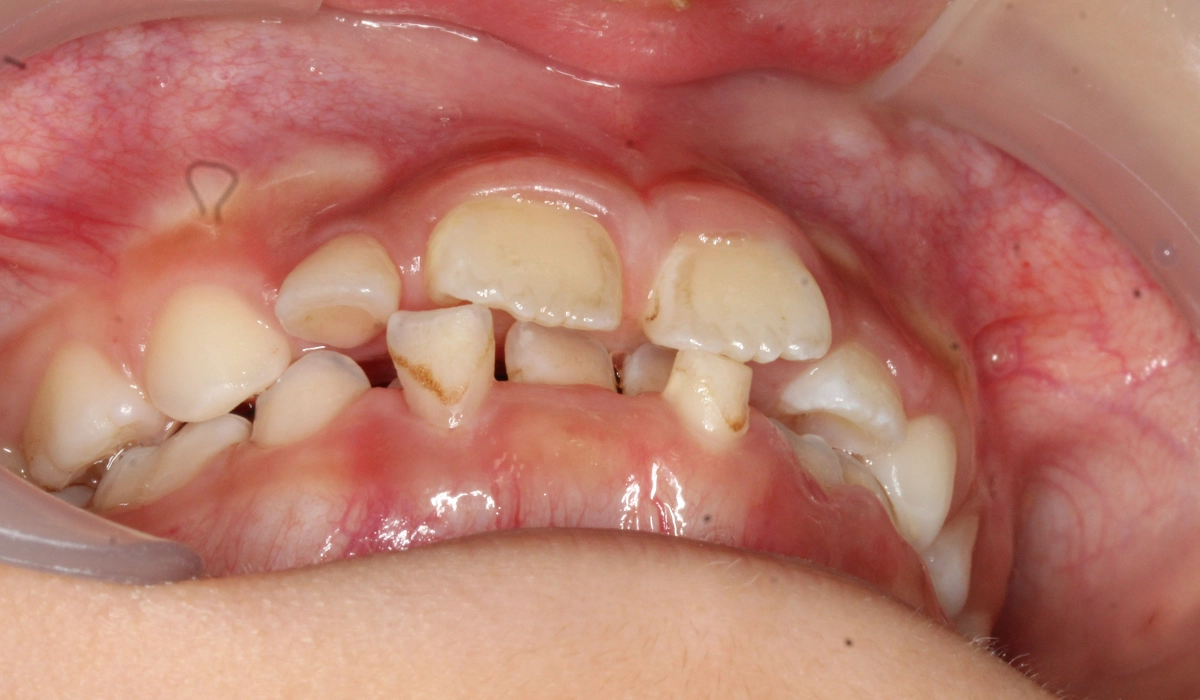

術前:前歯部あおり

術後:前歯部あおり